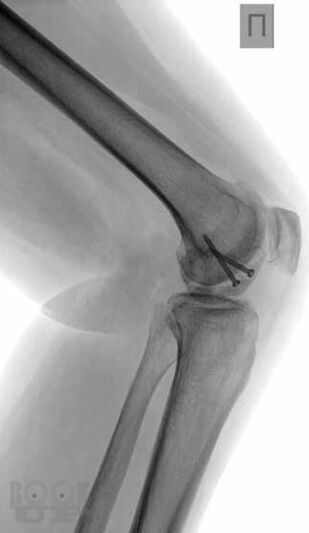

В основу книги положен многолетний опыт исследований коленного сустава в многопрофильной клинике с развитой ревматологической и ортопедической службами. Авторами приводится непредвзятое освещение возможностей современных методов лучевой диагностики патологии коленного сустава с адекватным позиционированием ультразвуковых исследований на различных этапах оказания медицинской помощи. Проанализирован опыт отечественных и зарубежных авторов, суммированы результаты многочисленных оригинальных собственных исследований. Подробно освещены особенности ультразвукового исследования широкого спектра патологических состояний и заболеваний травматического, воспалительного генеза, встречающихся у молодых и пожилых пациентов.

В книге представлен большой иллюстративный материал. Подробно изложена топографическая и ультразвуковая анатомия коленного сустава, рассмотрены технические особенности проведения исследования, варианты визуализации многочисленных патологических изменений.